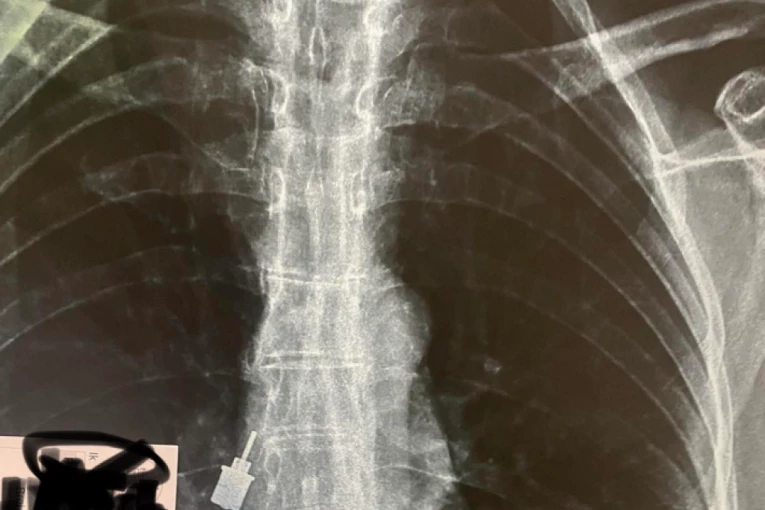

Foto: Printscreen/Twitter/docajoca

Sve se navodno odigralo u jednoj stomatološkoj ordinaciji u Beogradu, a "ključ" koji je žena udahnula ustvari je deo alata koji se koristi prilikom ugradnje i održavanja zubnog implanta, pisalo je u komentaru. Čim je shvatio šta se desilo, zubar je svoju pacijentkinju odvezao u Urgentni centar, gde su joj lekari odmah snimili grudni koš i ustanovili gde se strano telo nalazi.

Ubrzo je "ključ" izvađen bronhoskopom, a žena bez tegoba puštena kući, piše na društvenoj mreži, prenosi Alo.